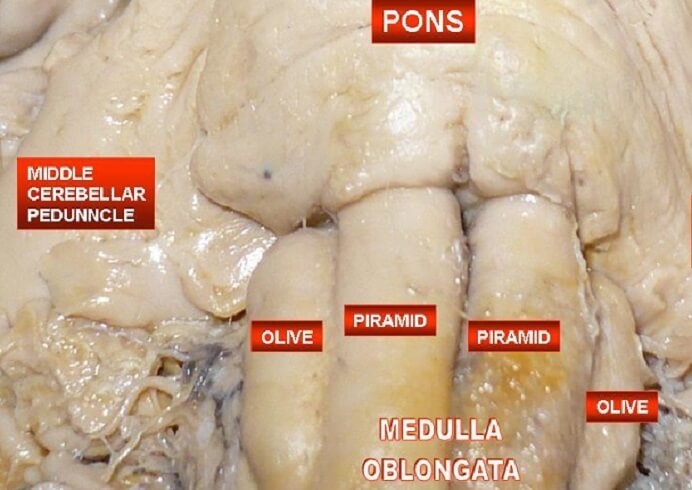

The Medulla Oblongata - Internal Structure - Vasculature

![Figure, Medulla oblongata] - StatPearls - NCBI Bookshelf](https://www.ncbi.nlm.nih.gov/books/NBK551589/bin/Medulla__oblongata.jpg)

Figure, Medulla oblongata] - StatPearls - NCBI Bookshelf

Olives of Medulla - AnatomyZone

The Medulla Oblongata and Pons

Surgical Anatomy of the Medulla Oblongata | SpringerLink

Medulla Oblongata: Definition, Structure And Functions